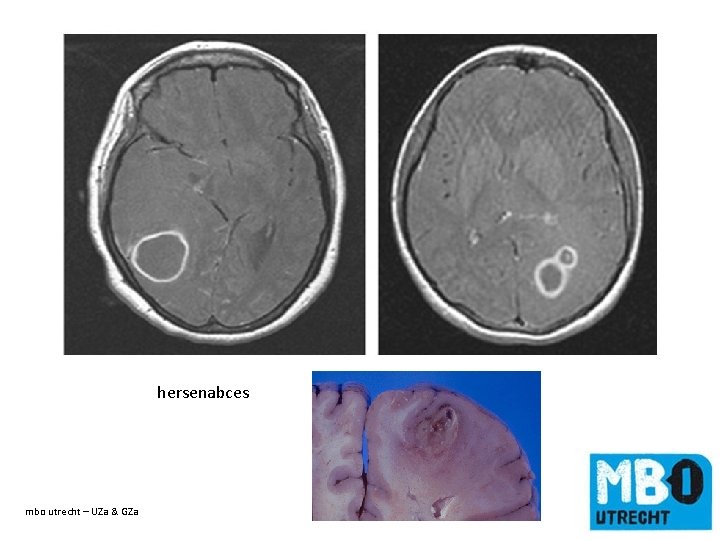

hersenabces mbo utrecht – UZa & GZa de titel van de dia